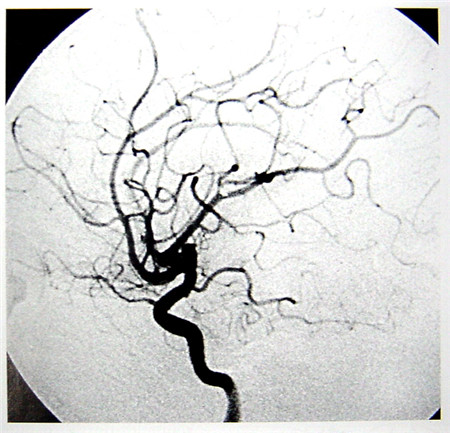

數(shù)字減影血管造影技術(shù)(Digital Subtraction Angiography,DSA)是一種新的X線成像系統(tǒng),是常規(guī)血管造影術(shù)和電子計算機圖像處理技術(shù)相結(jié)合的產(chǎn)物。DSA的成像基本原理是將受檢部位沒有注入造影劑和注入造影劑后的血管造影X線熒光圖像,分別經(jīng)影像增強器增益后,再用高分辨率的電視攝像管掃描,將圖像分割成許多的小方格,做成矩陣化,形成由小方格中的像素所組成的視頻圖像,經(jīng)對數(shù)增幅和模/數(shù)轉(zhuǎn)換為不同數(shù)值的數(shù)字,形成數(shù)字圖像并分別存儲起來,然后輸入電子計算機處理并將兩幅圖像的數(shù)字信息相減,獲得的不同數(shù)值的差值信號,再經(jīng)對比度增強和數(shù)/模轉(zhuǎn)換成普通的模擬信號,獲得了去除骨骼、肌肉和其它軟組織,只留下單純血管影像的減影圖像,通過顯示器顯示出來。通過DSA處理的圖像,使血管的影像更為清晰,在進行介入手術(shù)時更為安全。

超聲經(jīng)顱多普勒血流分析儀(TCD)提供的是實時動態(tài)的腦血管的血流動力學(xué)資料。核磁共振血管成像(MRI)提供的是大腦實質(zhì)細胞的損壞與形態(tài)學(xué)上改變的影像學(xué)資料 。數(shù)字減影血管造影(DSA)提供的是腦血管瞬間形態(tài)學(xué)上的變化,且有創(chuàng)傷。

數(shù)字減影血管造影DSA腦血管圖像顯示                                                      核磁共振MRI掃描腦組織圖像